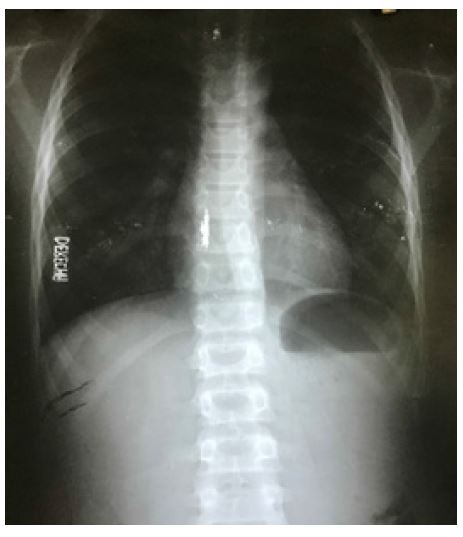

En el examen físico se encontró talla 165,7 cm (talla para la edad [T/E] > 97 percentil), apéndice preauricular unilateral derecho, máculas hipocrómicas que siguen las líneas de Blaschko en miembro superior derecho y región anterosuperior del hemitórax ipsilateral (figura 2), hernia umbilical, agenesia pectoral unilateral derecha, hiperlaxitud articular de las extremidades y escoliosis dorsolumbar (figura 3).

La imagen describe la presencia de escoliosis dorsolumbar

Algunos autores(5,6) expone que el sistema osteomioarticular representa el segundo sistema más afectado, con alteraciones en la columna vertebral (cifosis o escoliosis) y el esqueleto axial (sindactilia y polidactilia). En este caso se manifestó la escoliosis, además de otras alteraciones que pudieran estar asociadas o no a dicha entidad, como la hiperlaxitud articular y la agenesia pectoral, reportadas igualmente en la literatura(7). Sin embargo, estas lateraciones no son reconocidas como patrones de dicha enfermedad.